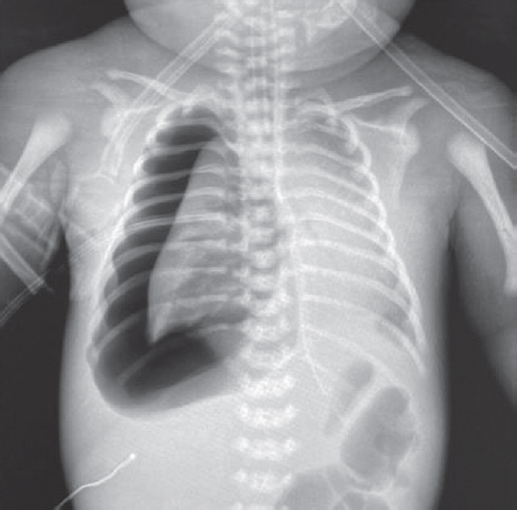

On day 12 of life, the child had regular spontaneous breathing, restoration of protective reflexes, and muscle tone; thus, the child was extubated, and switched to non-invasive ALV with FiO2 of 0.3, PEEP of 5 cm H2O, and f of 7.0 per min. No pronounced pathological changes were noted in the control radiograph of the chest organs (Fig. 8).

Fig. 8. Chest X-ray of newborn with spontaneous breathing

Рис. 8. Рентгенограмма органов грудной клетки новорожденного на фоне спонтанного дыхания